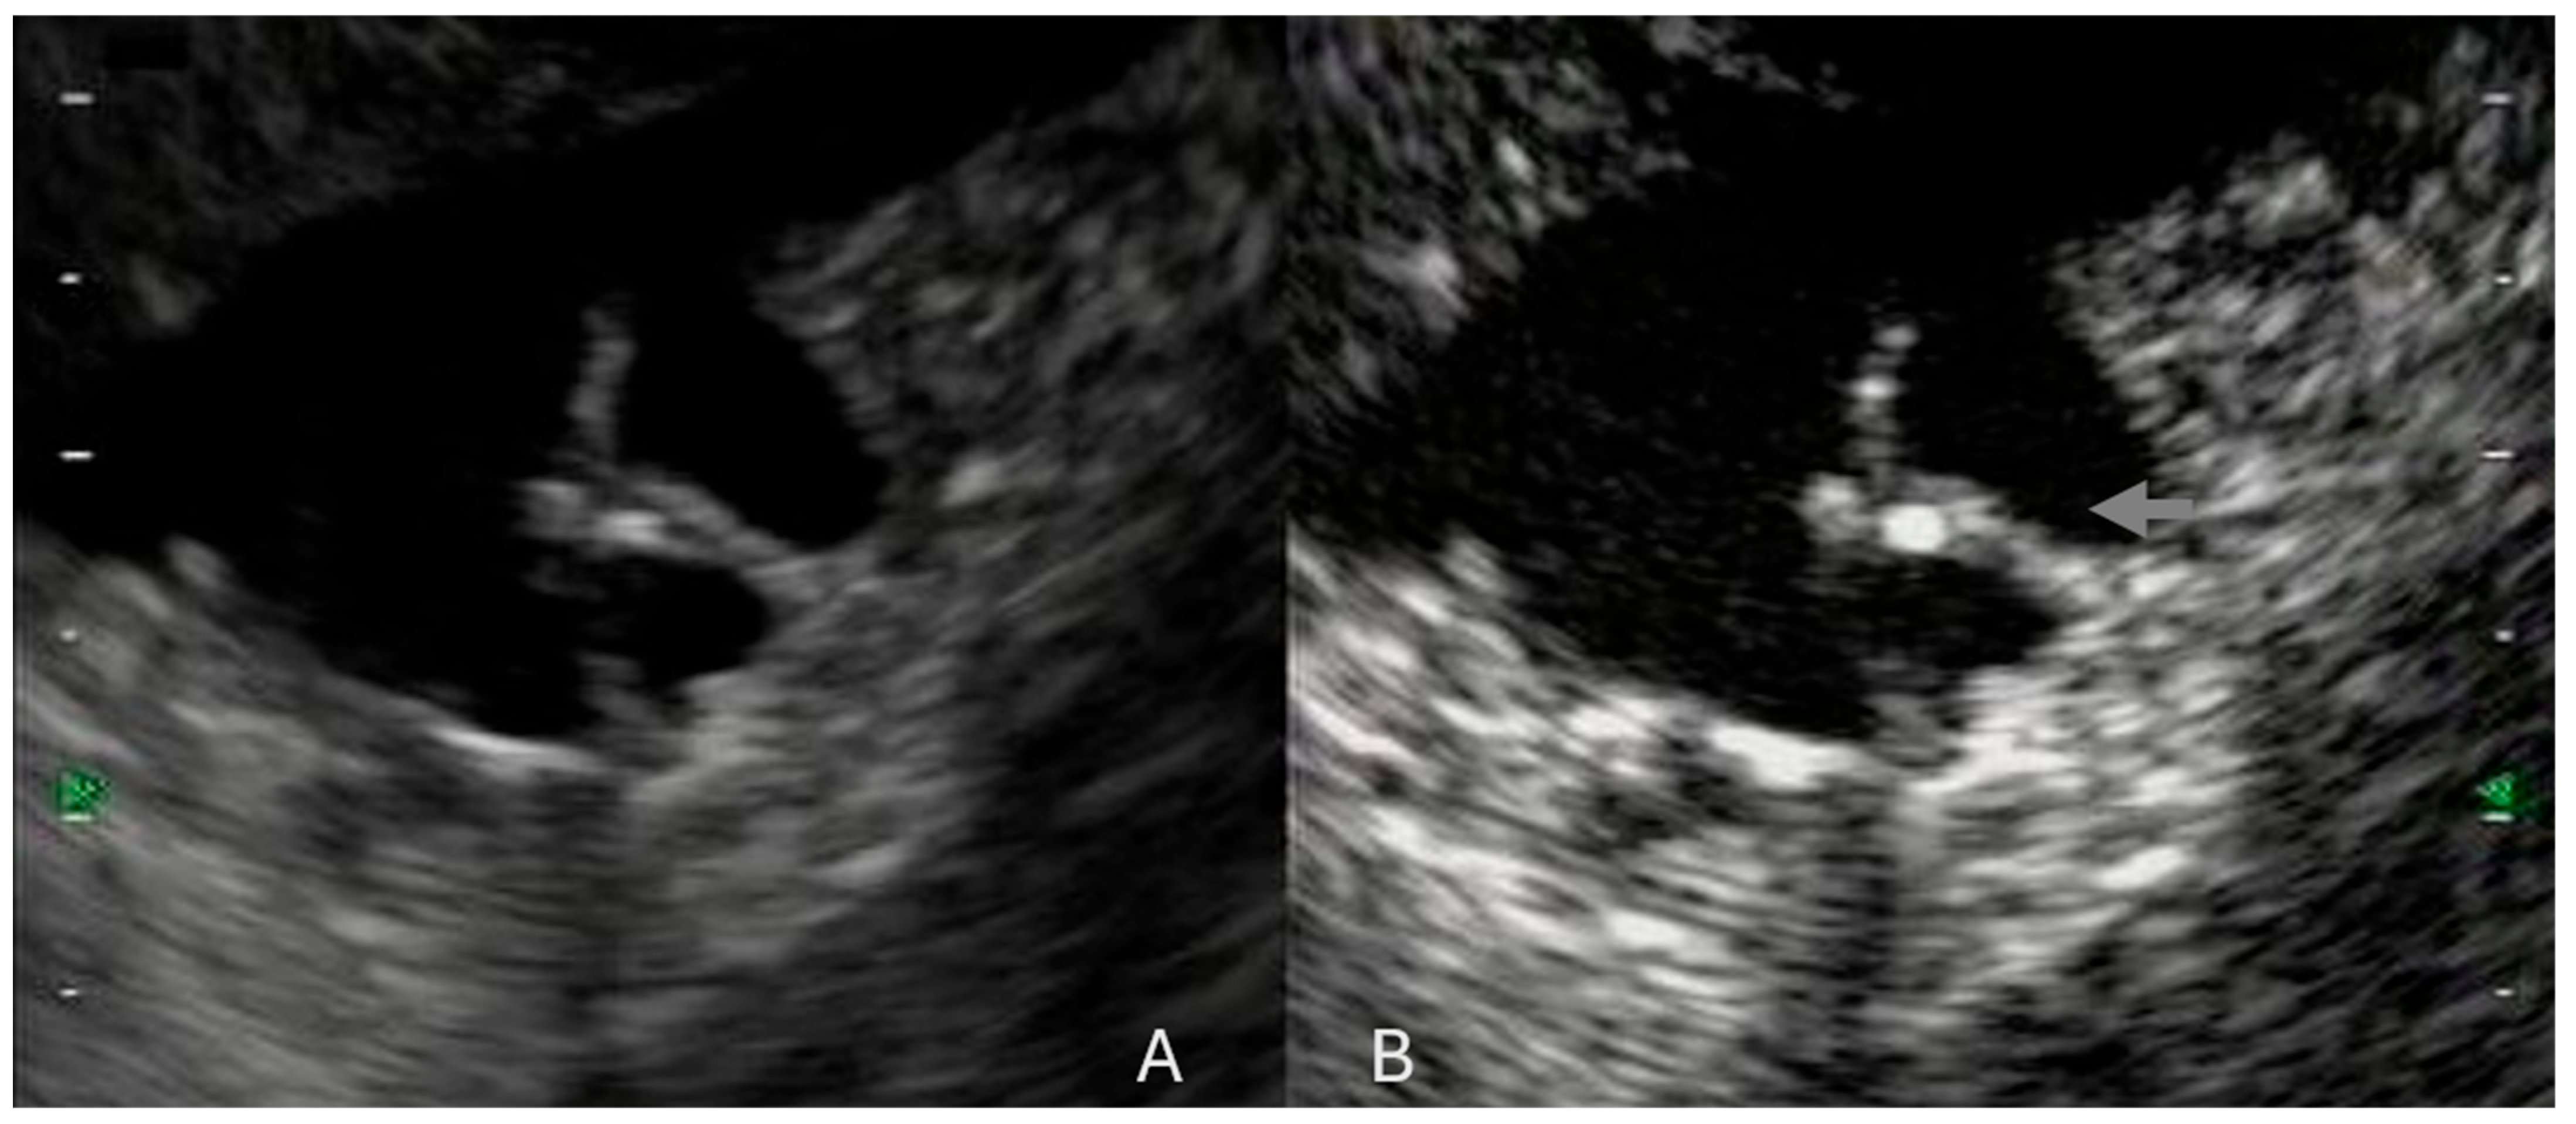

- Ohno, E.; Itoh, A.; Kawashima, H.; Ishikawa, T.; Matsubara, H.; Itoh, Y.; Nakamura, Y.; Hiramatsu, T.; Nakamura, M.; Miyahara, R.; et al. Malignant Transformation of Branch Duct-Type Intraductal Papillary Mucinous Neoplasms of the Pancreas Based on Contrast-Enhanced Endoscopic Ultrasonography Morphological Changes: Focus on Malignant Transformation of Intraductal Papillary Mucinous Neoplasm Itself. Pancreas 2012, 41, 855–862. [Google Scholar] [CrossRef] [PubMed]

- Kamata, K.; Kitano, M.; Omoto, S.; Kadosaka, K.; Miyata, T.; Yamao, K.; Imai, H.; Sakamoto, H.; Harwani, Y.; Chikugo, T.; et al. Contrast-Enhanced Harmonic Endoscopic Ultrasonography for Differential Diagnosis of Pancreatic Cysts. Endoscopy 2016, 48, 35–41. [Google Scholar] [CrossRef] [PubMed]

- Yamashita, Y.; Kawaji, Y.; Shimokawa, T.; Yamazaki, H.; Tamura, T.; Hatamaru, K.; Itonaga, M.; Ashida, R.; Kawai, M.; Kitano, M. Usefulness of Contrast-Enhanced Harmonic Endoscopic Ultrasonography for Diagnosis of Malignancy in Intraductal Papillary Mucinous Neoplasm. Diagnostics 2022, 12, 2141. [Google Scholar] [CrossRef]